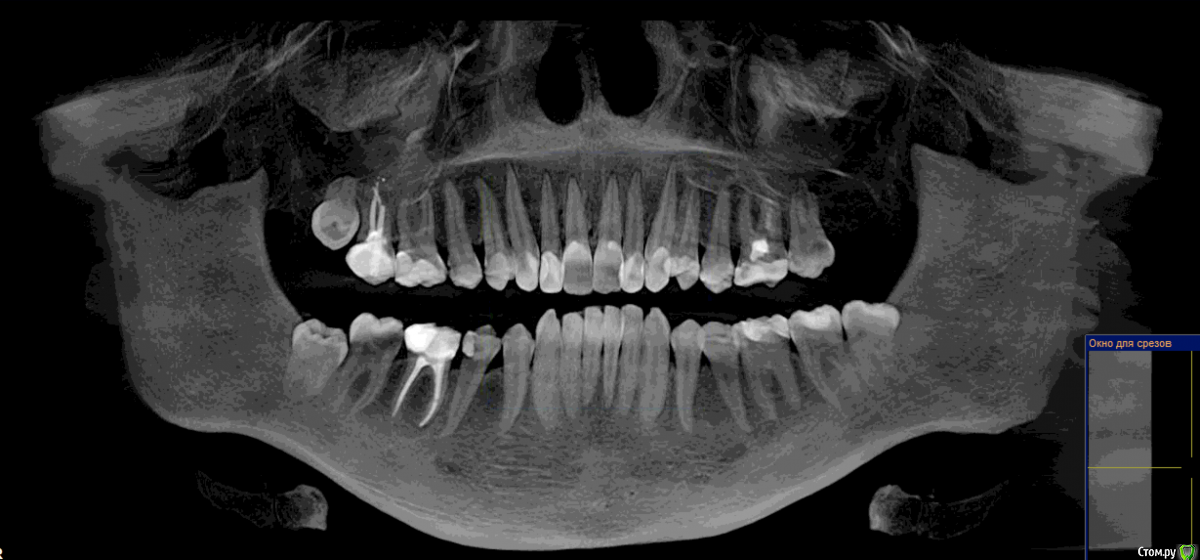

mayron Опубликовано 19 ноября, 2017 Поделиться Опубликовано 19 ноября, 2017 Добрый день! Прокомментируйте пож-та план лечения 16, 27, 25, 45 - лечение пульпита.15, 14, 23, 24, 35, 36, 37 - лечение кариеса18, 38, 48, 26 - удаление Точно ли везде нужно лечить пульпит? И можно ли сохранить 26ой зуб, или нет смысла? Ссылка на комментарий

Гарриевич Опубликовано 20 ноября, 2017 Поделиться Опубликовано 20 ноября, 2017 Пульпиты однозначно или врач будет смотреть по ситуации?Выложите срезы в области 26: по какой причине говорят удалять? Ссылка на комментарий

IvanK Опубликовано 20 ноября, 2017 Поделиться Опубликовано 20 ноября, 2017 Прокомментируйте пож-та план лечения очень похоже по поводу 26 - надо смотреть срезы и определиться с Вашими желаниями) Ссылка на комментарий

mayron Опубликовано 7 декабря, 2017 Автор Поделиться Опубликовано 7 декабря, 2017 Тему можно закрывать, всем спасибо, лечение в процессеУдалили 8ки и 26Пролечили пульпит Ссылка на комментарий